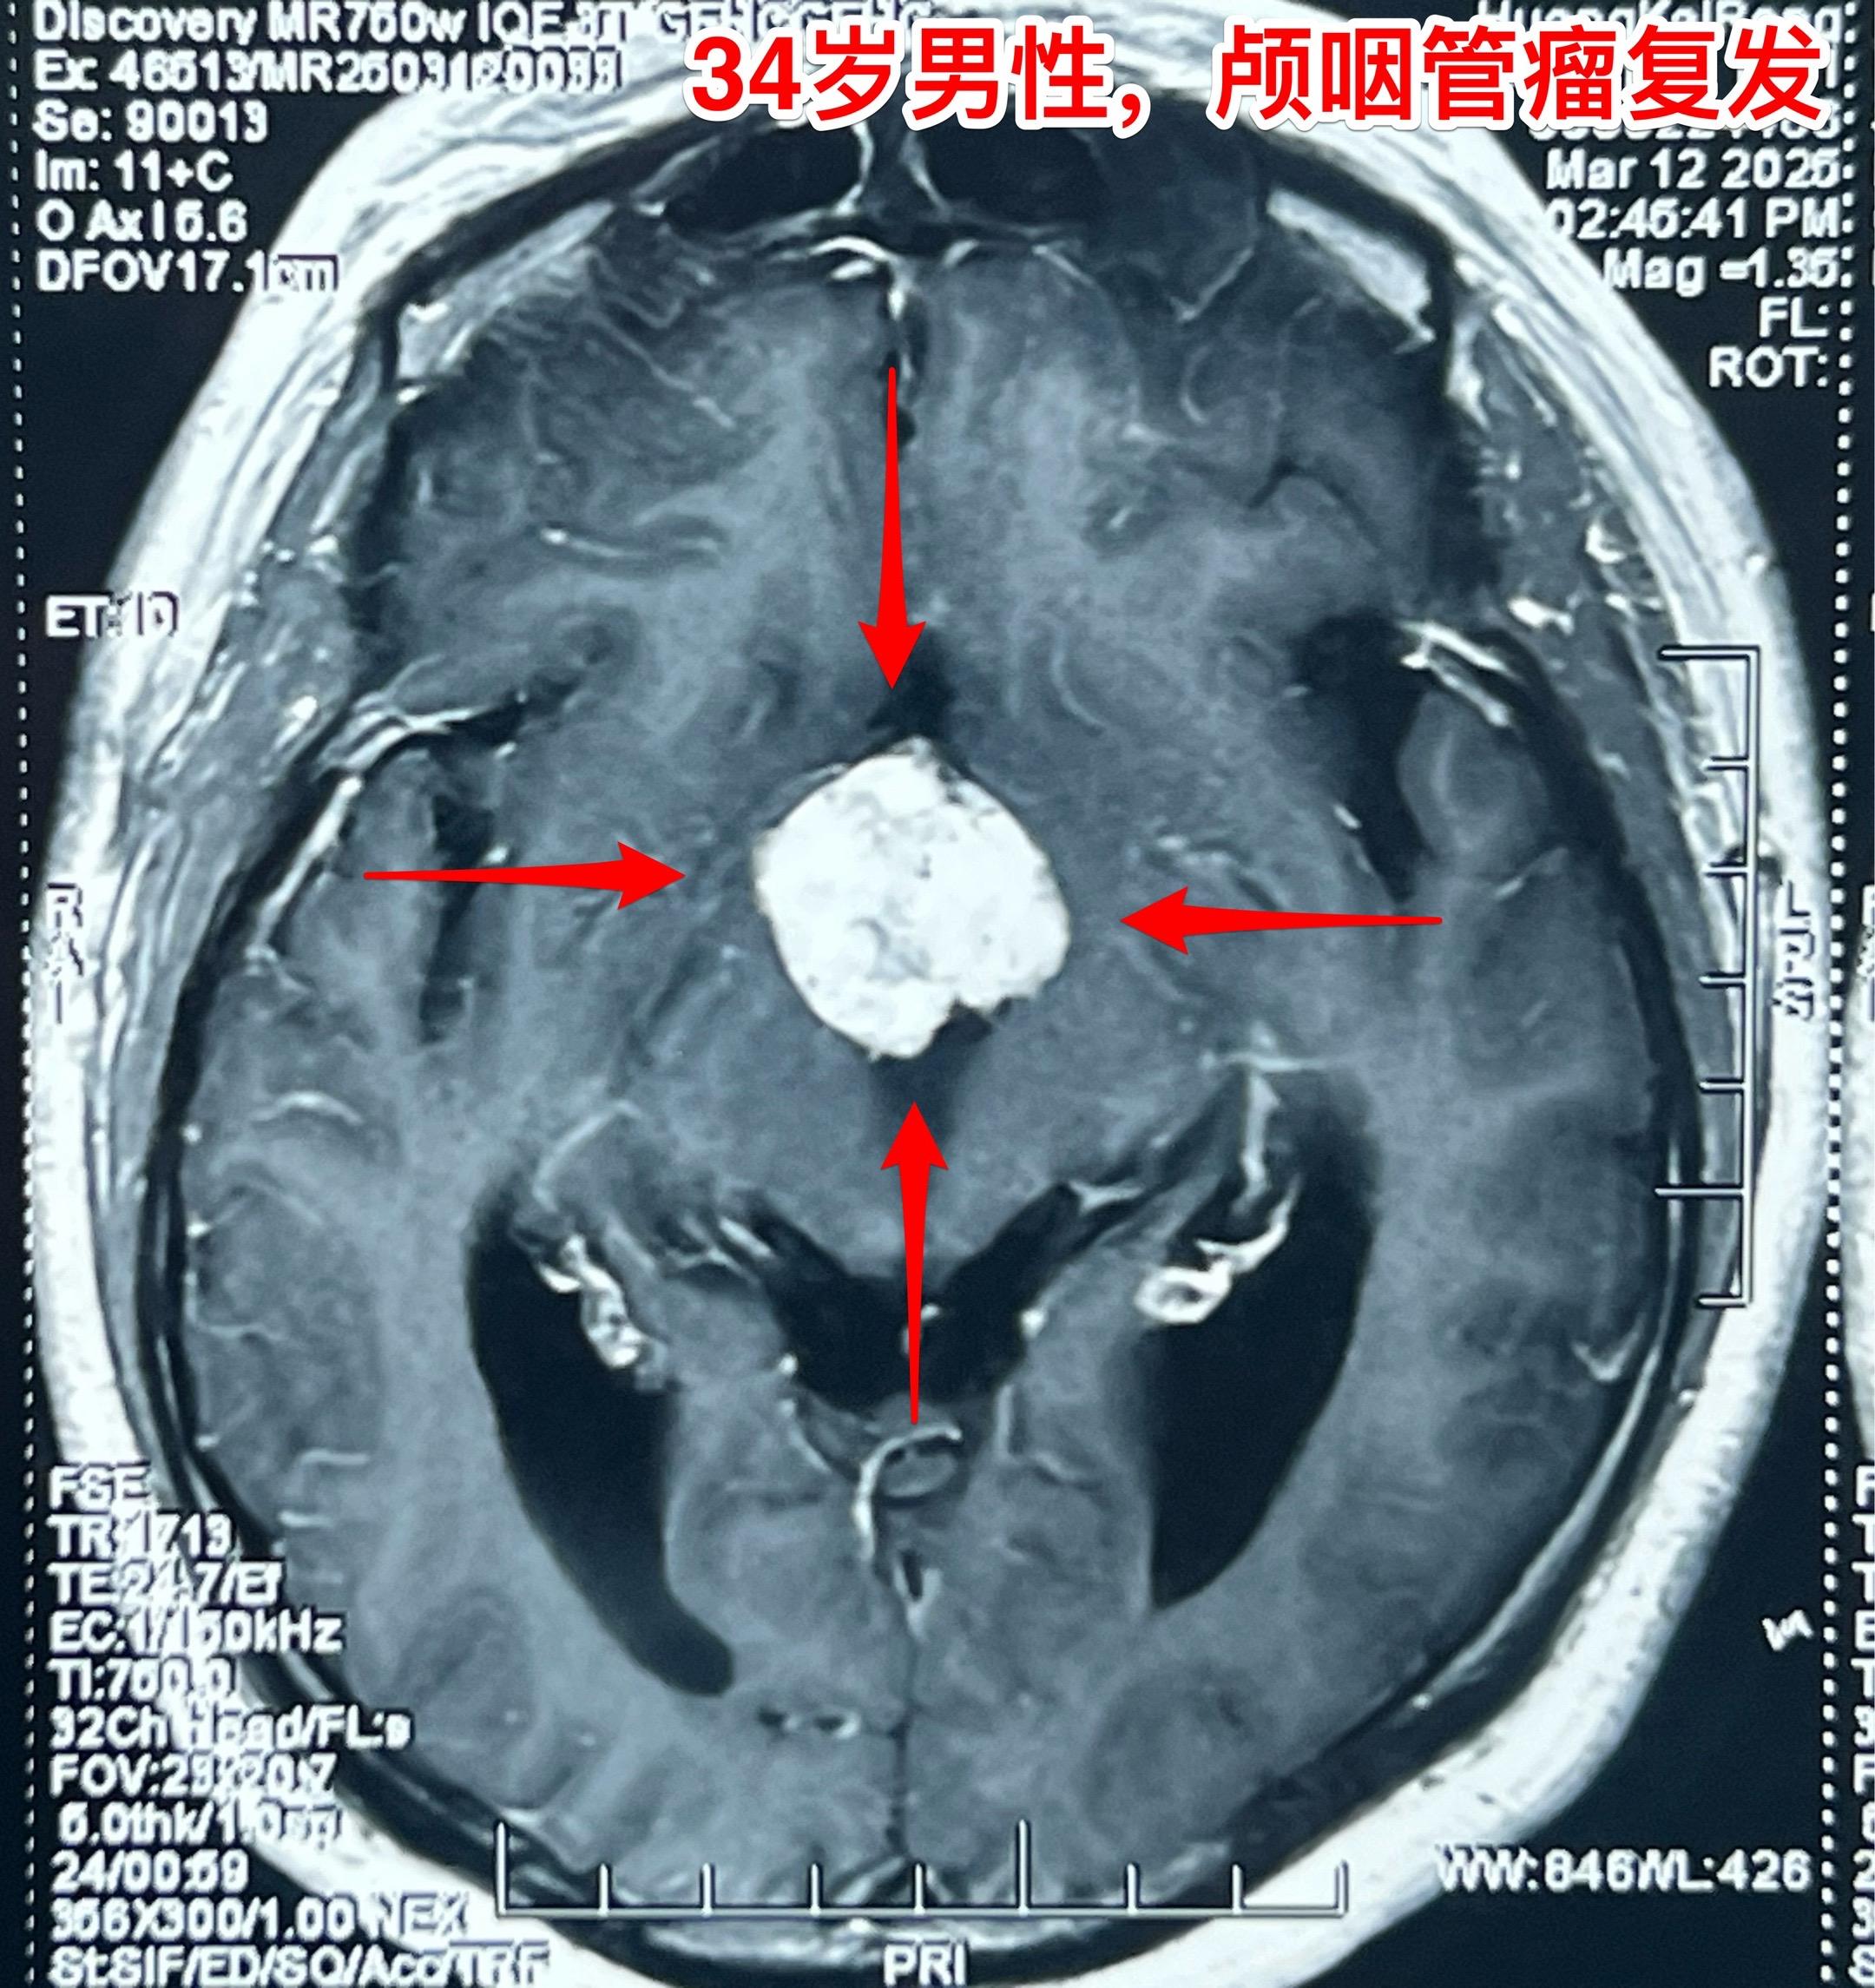

乳头型和造釉型颅咽管瘤的混合型存在吗?34岁男性,广东省惠州市人。一年前因视力下降发现颅咽管瘤,在广东省某医院行开颅手术切除一部分肿瘤。肿瘤复发了来三博脑科医院找我治疗。 第一次手术后病理报告考虑是乳头型颅咽管瘤和造釉型颅咽管瘤的混合型(太罕见了)。手术中还留置了一个动脉瘤夹子、一个Ommaya囊。 昨日作了开颅手术,术中看见肿瘤血供十分丰富,和第三脑室壁及大脑后动脉粘连。手术经历9.5个小时,肿瘤得到完全切除。术后病人的精神状态及四肢活动均很好。希望以后肿瘤不复发。等待病理